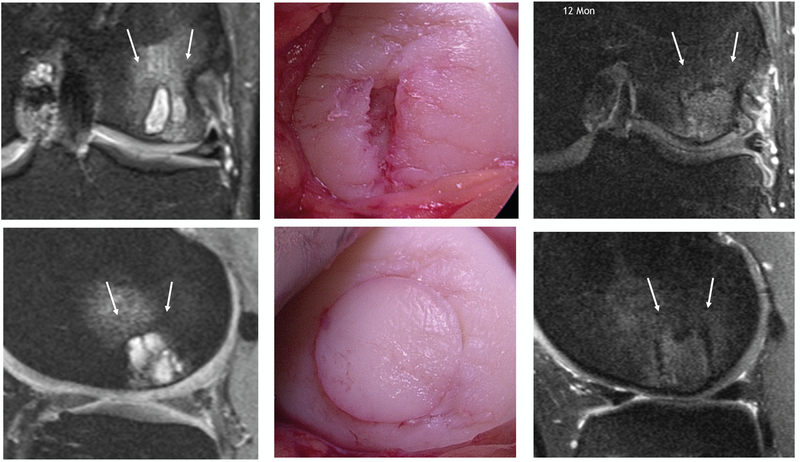

The old adage “hyaline cartilage does not repair” continues to hold true and should be communicated to patients, despite all modern cartilage restoration procedures. Whilst all surgery tech-niques including the latest generation of modern autologous chondrocyte transplantation (ACT) allows replacing the cartilage defect with a similar, histologically high-quality (hyaline-like) structure, this transplant is not identical to natural cartilage (Fig 3).

Matrix-associated autologous chondrocyte transplantation (M-ACT)

For the M-ACT it is recommended in clinical practice to compile the consent forms and any reporting to the chondrocyte registry in advance and to arrange the harvesting and implant dates with the patient directly according to the cell expansion time. During the first procedure an arthroscopy is performed to confirm the indication and the defect is debrided thoroughly (Fig. 25).

Chondrocyte harvesting is performed after careful defect documentation. The cells can be cultivated in gel form, membrane associated for suture fixation or as spheroids. Depending on the system, cartilage biopsies are harvested for cell cultivation (e.g. 2−3 small cylinders), usually from the cranial notch (Fig. 26). The biopsy cylinders are sent for cultivation. This is followed by the realignment osteotomy in the same session.

The chondrocyte implant is implanted in a second procedure according to the matrix used. When using gel-like matrix or spheroids, the substrate can usually be reinserted by arthroscopy without problems. Draining of the arthroscopy water is usually sufficient for defects in the femorotibial area. In case of poorly accessible defects (dorsal condyles/retropatellar) the option of using CO2 gas from general surgery can be considered to better visualize the defect. The matrix forms a gel within a few minutes, has a moderate haemostatic effect and remains within the defect after moving the joint through its full range. Performing the necessary defect debridement during the first stage has proven successful, because further extensive manipulation of the base of the defect can result in increased subchondral haemorrhage and poorer view. If inferior subchondral bone has to be constructed, then this is augmented prior to the M-ACT implantation by autologous spongiosa or corticospongious chips. The chondrocyte implantation can of course also be per-formed via a mini-open arthrotomy. The application sequence is identical (Fig. series 27).